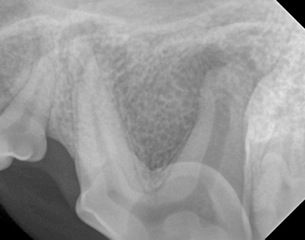

x-ray of the dog’s maxillary premolar

- This is the left maxillary fourth premolar tooth (sometimes referred to as a carnassial tooth). Dogs typically have four maxillary and four mandibular premolars. The maxillary fourth premolar is a three rooted tooth with two mesial and one distal roots

- There is evidence of peri-apical bone loss affecting all three roots of the left maxillary premolar tooth. This will be associated with inflammation and often infection in this area

- The most likely cause is a complicated crown fracture. Complicated crown fractures are tooth fractures that expose the pulp. Pulp exposure will result in infection and inevitable pulp necrosis

- The treatment options for this tooth are either extraction or endodontic treatment. Teeth that have pulp exposure should always be treated. Extraction of teeth in dogs is a surgical procedure which often involves raising a muco-periosteal flap, removing bone and sectioning the tooth into single rooted sections. It is a significant surgical procedure with potential complications. Endodontic treatment would involve root canal treatment in this case. The benefits of endodontic treatment are that it is non-invasive, there are fewer potential complications and an important strategic tooth is preserved